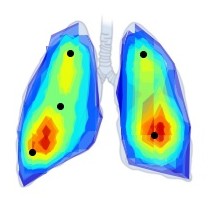

Chest Imaging

Bad Normal Good